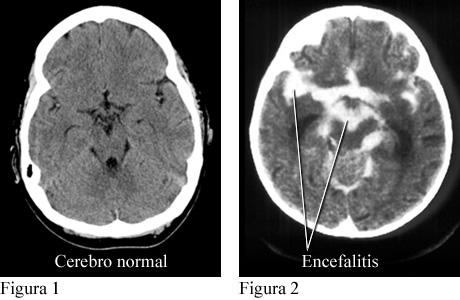

Tomografías computarizadas de un cerebro normal y de un cerebro con encefalitis

Cortesía de Paul Traughber, M.D., Boise, Idaho.

La figura 1 es una tomografía computarizada (CT, por sus siglas en inglés) de un cerebro normal. La figura 2 es una CT que muestra una acumulación de material de contraste en zonas infectadas y alrededor del cerebro como resultado de una encefalitis.